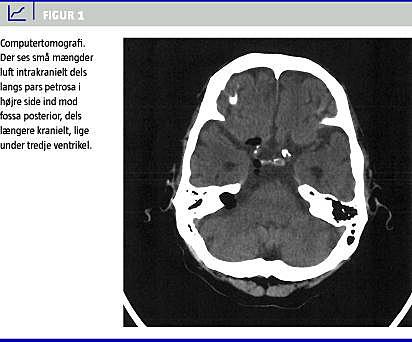

Ved en akut computertomografi (CT) af cerebrum (Figur 1 ) sås der sløring af mastoidet på højre side og små mængder luft intrakranielt dels langs pars petrosa i højre side ind mod fossa posterior, dels i højre side af pentagoncisternen. Desuden sås der små luftbobler længere kranielt, lige under tredje ventrikel. Endvidere kunne der ses en bred ossøs åbning fra pars petrosa ind mod den cerebellopontine vinkel. Patienten blev sløv, og temperaturen steg til 39,4 °C. Blodprøverne viste neutrofil leukocytose med en koncentration af hhv. leukocytter på 16,5 mia./l og C-reaktivt protein på 56 mg/l. På mistanke om CNS-infektion fik patienten foretaget lumbalpunktur. Den efterfølgende analyse af cerebrospinalvæsken viste et totaltproteinniveau på 2,5 g/l, et leukocyttal på 2,349 mia./l og relativt mange polynukleære celler. Mikroskopien viste pneumokokker.